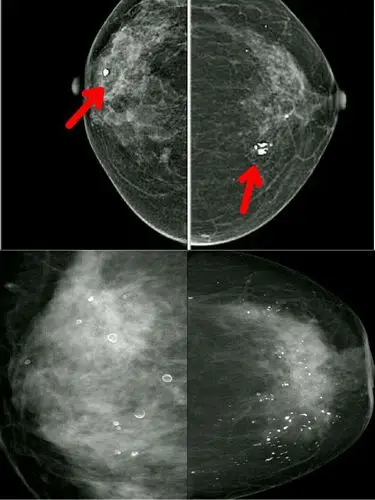

乳腺癌钼靶影像 - 好大夫在线

阅乳大师61钼靶篇492402乳腺影像病例发现左乳肿物3月余